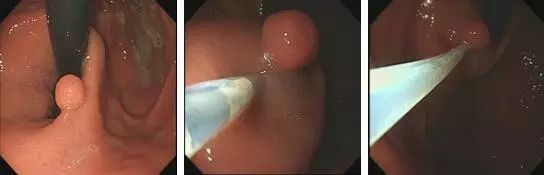

②内镜下黏膜剥离术(EMR):

即在内镜下将病变黏膜剥离,并用高频电流完整切除。

为什么说热活检钳胃肠息肉是怎么长出来的?有什么危害?如何预防和治疗?_https://www.jmylbn.com_新闻资讯_第9张1.发现息肉;2.于息肉基底部注射,抬起征阳性;3.圈套器套扎息肉基底部

为什么说热活检钳胃肠息肉是怎么长出来的?有什么危害?如何预防和治疗?_https://www.jmylbn.com_新闻资讯_第10张

4.息肉切除术后;5.钛夹夹闭创面